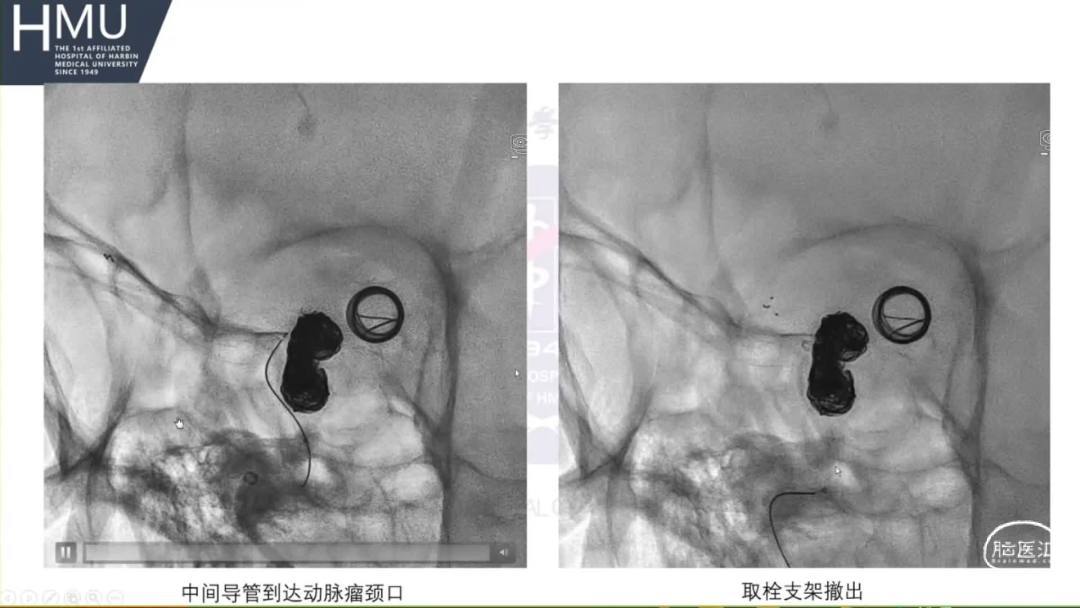

21:00覆膜支架置入术